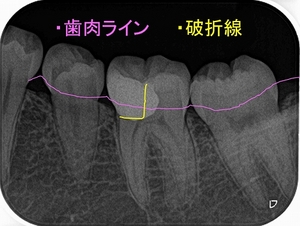

とりあえず根管治療をして治すことにしましたが、

近心根にはパフォーレーション 手付かずの遠心根には破折線が見られ、

患者さんにどうします!?遠心根はまず残せない、近心根は残すことが出来るがパフォーレーションの位置的に長く持たない可能性がある。

不思議なんですが、遠心根は根管治療していないにも関わらず折れてきている。

患者さんと話し合い、近心根はヘミセクションをして残す 遠心根は抜歯